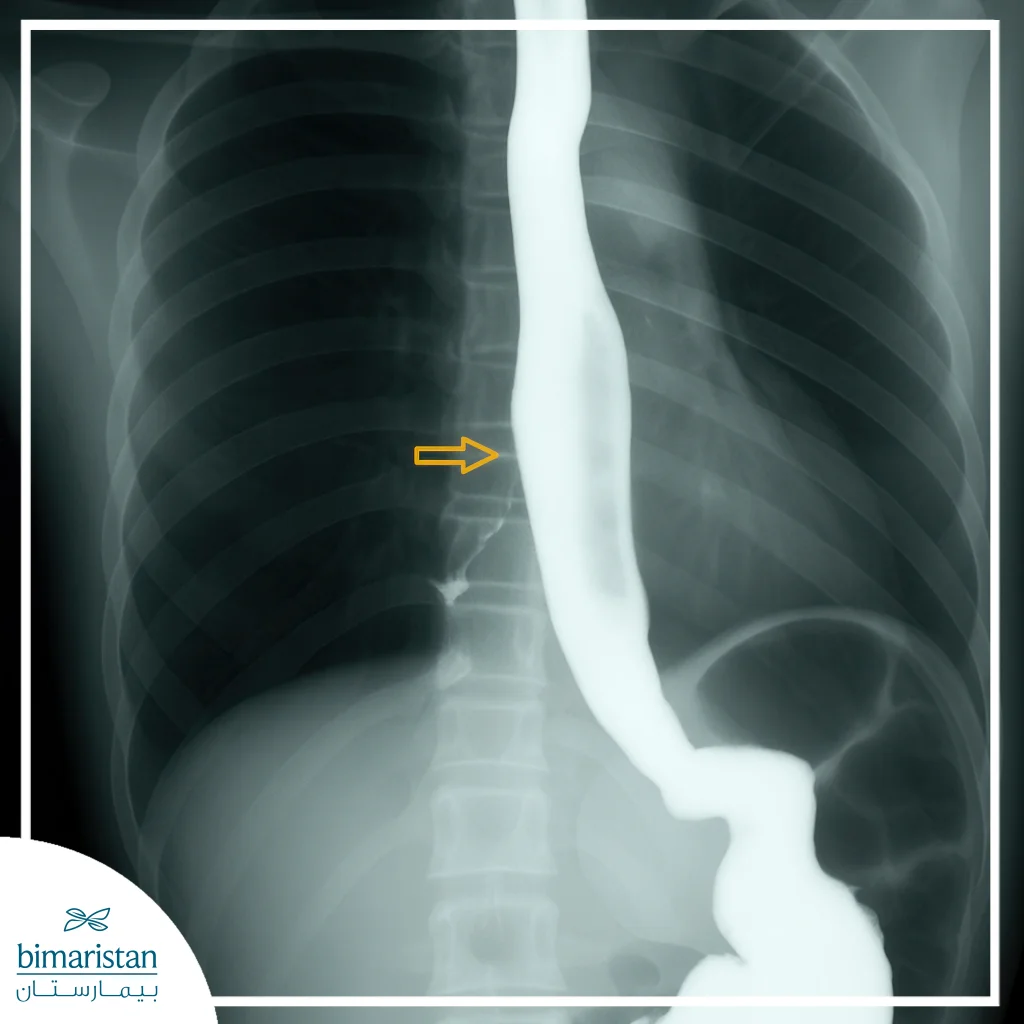

الأشعة السينية مع الباريوم (Barium Swallow)

يتم استخدام هذه التقنية لتصوير المريء بعد ابتلاع مادة تحتوي على الباريوم، مما يسمح للطبيب برؤية أي تسرب للمادة إلى الشعب الهوائية. هذه الطريقة فعالة لتحديد حجم الناسور وشكله، كما تساعد في التخطيط الجراحي أو التنظيري المناسب للعلاج.